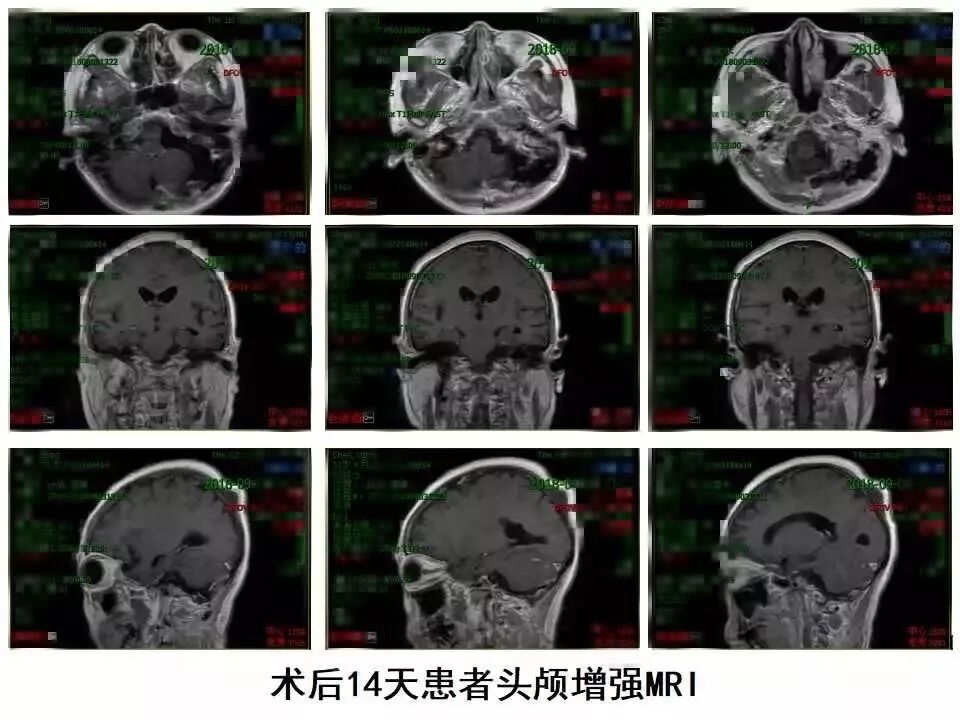

“双镜联合”切除A型颈静脉孔区神经鞘瘤

术后14天患者录像

术后14天患者面部表情

术后14天患者语言情况

术后14天患者饮水情况

术后14天患者行走录像